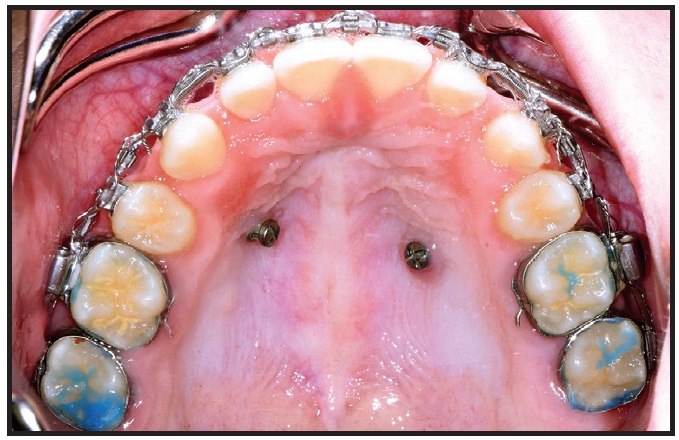

This example shows a 27-year-old female patient with a compensated Class II malocclusion (see attached video in the online version of this article). Note that the lower incisors are excessively proclined (IMPA of about 110°) in the pretreatment lateral cephalogram (Fig. 1).

Presenting to our office 18 months after completing a previous treatment, the patient had lost her lower left central incisor (Fig. 2). In an effort to reduce the lower-incisor proclination, the teeth were torqued at levels that might have appeared to be customary but were incompatible with the alveolar-housing anatomy.

Before torquing, we as orthodontic specialists need to understand the alveolar-housing anatomy to prevent dehiscence and fenestrations.

Fig. 1 Patient with compensated Class II malocclusion (Class I dental, Class II skeletal) before treatment. Lateral cephalogram indicates proclined lower incisors, with IMPA of about 110°.

Fig. 2 A. Three-dimensional volumetric reconstruction of cone-beam computed tomography (CBCT) taken 18 months after patient completed treatment with previous orthodontist, showing loss of lower left central incisor and dehiscence of remaining lower-incisor roots from alveolar housing. B. Sagittal CBCT slices of upper right canine, first premolar (missing), second premolar, and first molar, confirming root positions incompatible with alveolar-housing anatomy.